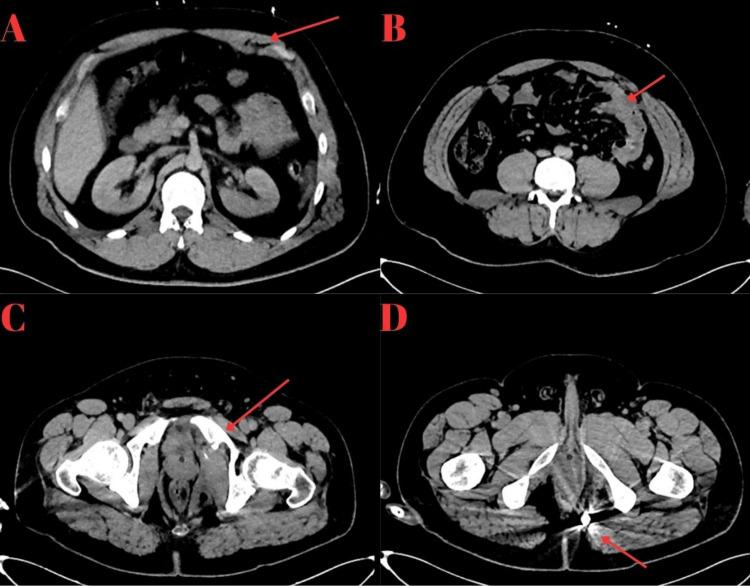

Gunshot wounds (GSWs) to the thoracic region are often associated with high mortality due to the injury of vital organs such as the heart, lungs, and aorta. Abnormal bullet trajectories complicate diagnosis and treatment, particularly when the bullet remains lodged within the body and no exit wound is present. This case report describes a rare instance of a gunshot wound entering through the anterior chest wall and ultimately lodging in the rectal region without an exit wound. Initial chest and abdominal imaging showed no acute pathology; however, advanced imaging, including contrast-enhanced abdominal and chest computed tomography (CT) scans, revealed that the bullet followed an atypical trajectory, traversing the small bowel, bladder, and pubic ramus before settling in the inferior ischioanal region. The patient underwent successful surgical intervention for both bowel and bladder injuries. This case highlights the importance of comprehensive secondary assessments, including advanced imaging, in identifying abnormal bullet trajectories and guiding appropriate management.

胸部枪伤(GSWs)常因心脏、肺和主动脉等重要器官受伤而导致高死亡率。异常的子弹轨迹使诊断和治疗变得复杂,尤其是当子弹留在体内且没有出口伤口时。本病例报告描述了一个罕见的案例,即枪伤从前胸壁进入,最终停留在直肠区域且没有出口伤口。最初的胸部和腹部影像学检查未显示急性病变;然而,包括腹部和胸部增强计算机断层扫描(CT)在内的高级影像学检查显示,子弹沿着非典型轨迹行进,穿过小肠、膀胱和耻骨支,然后停留在坐骨肛门下区域。患者因肠道和膀胱损伤接受了成功的手术干预。本病例强调了全面的二次评估(包括高级影像学检查)在识别异常子弹轨迹和指导适当治疗方面的重要性。